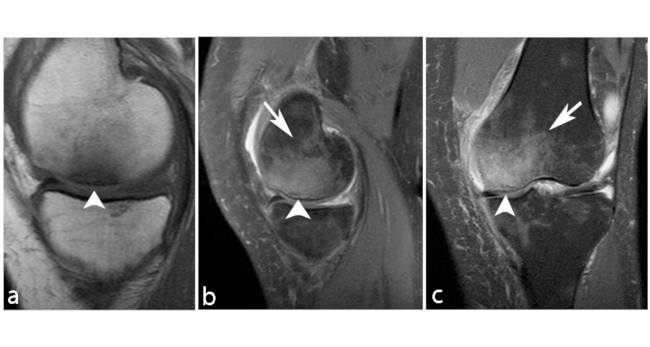

La ON de rodilla afecta a los cóndilos femorales y platillo tibial, denominándose enfermedad de Ahlback cuando se presenta de forma espontánea debido a osteoporosis e insuficiencia subcondral.11 Se presenta alrededor de los 60 años, con frecuencia en el sexo femenino en una relación 3 a 1. El cóndilo femoral interno es el sitio más frecuente afectado debido a ser un área de carga, siendo generalmente unilateral.

Los primeros estadios de la lesión se caracterizan por una fractura subcondral sin asociación de hallazgos osteonecróticos, reconocida en RM por una imagen lineal de baja señal ponderada en T1, subcortical, y edema periférico extenso mejor evidenciado en secuencias ponderadas en T2. Al avanzar su estadio, estas lesiones osteonecróticas muestran cambios distales por una cicatrización deficiente, lo que genera reacción y formación de cartílago con tejido fibroso indicativo de retraso o falta de unión.11

En RM en secuencia ponderada en T1, la intensidad de señal de la grasa de la médula ósea del cóndilo femoral afectado es reemplazada por un área con baja señal, asociada a una periferia de aún más baja señal (►Figs. 4 y 5).8 En la secuencia ponderada en T2 se visualiza lesión central hipointensa con área de señal alta periférica en relación al patrón de edema de la médula ósea (►Fig. 6).11

Tiene un buen pronóstico cuando el segmento que se afecta es pequeño o el tratamiento es adecuado (descarga completa de la pierna afectada asociado a analgésicos). En caso contrario, evoluciona a una artrosis grave de rodilla con dolor mecánico invalidante. El hallazgo que más influye en la evolución, es el volumen de la zona condílea de carga que se ha afectado, siendo un pronóstico desfavorable al afectarse >50% del tamaño con tendencia al colapso óseo y artrosis secundaria.5,11